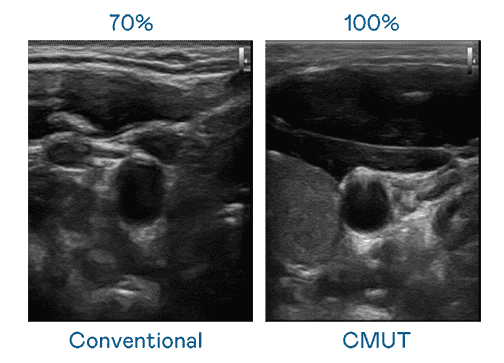

CMUT 技术是一种用电容式微机电元件来产生超音波讯号的技术。。。。与传统 PZT 压电式技术相比,,,,CMUT 频宽增加 30%,,,更宽频的超音波讯号让影像解析度大幅提升,,,是实现高影像品质医疗超音波扫描、、、、促进精准医疗发展的关键技术。。。

大频宽带来超清晰影像

超音波影像的解析度高低,,,首先取决于探头能发出的讯号频宽。。。尊龙集团 CMUT 可提供高清晰的超音波讯号,,,提供高频宽、、高灵敏度、、、影像纹理细节更高的超音波影像,,协助医护人员缩短影像判读时间及利用精准的医疗影像进行诊断。。。。